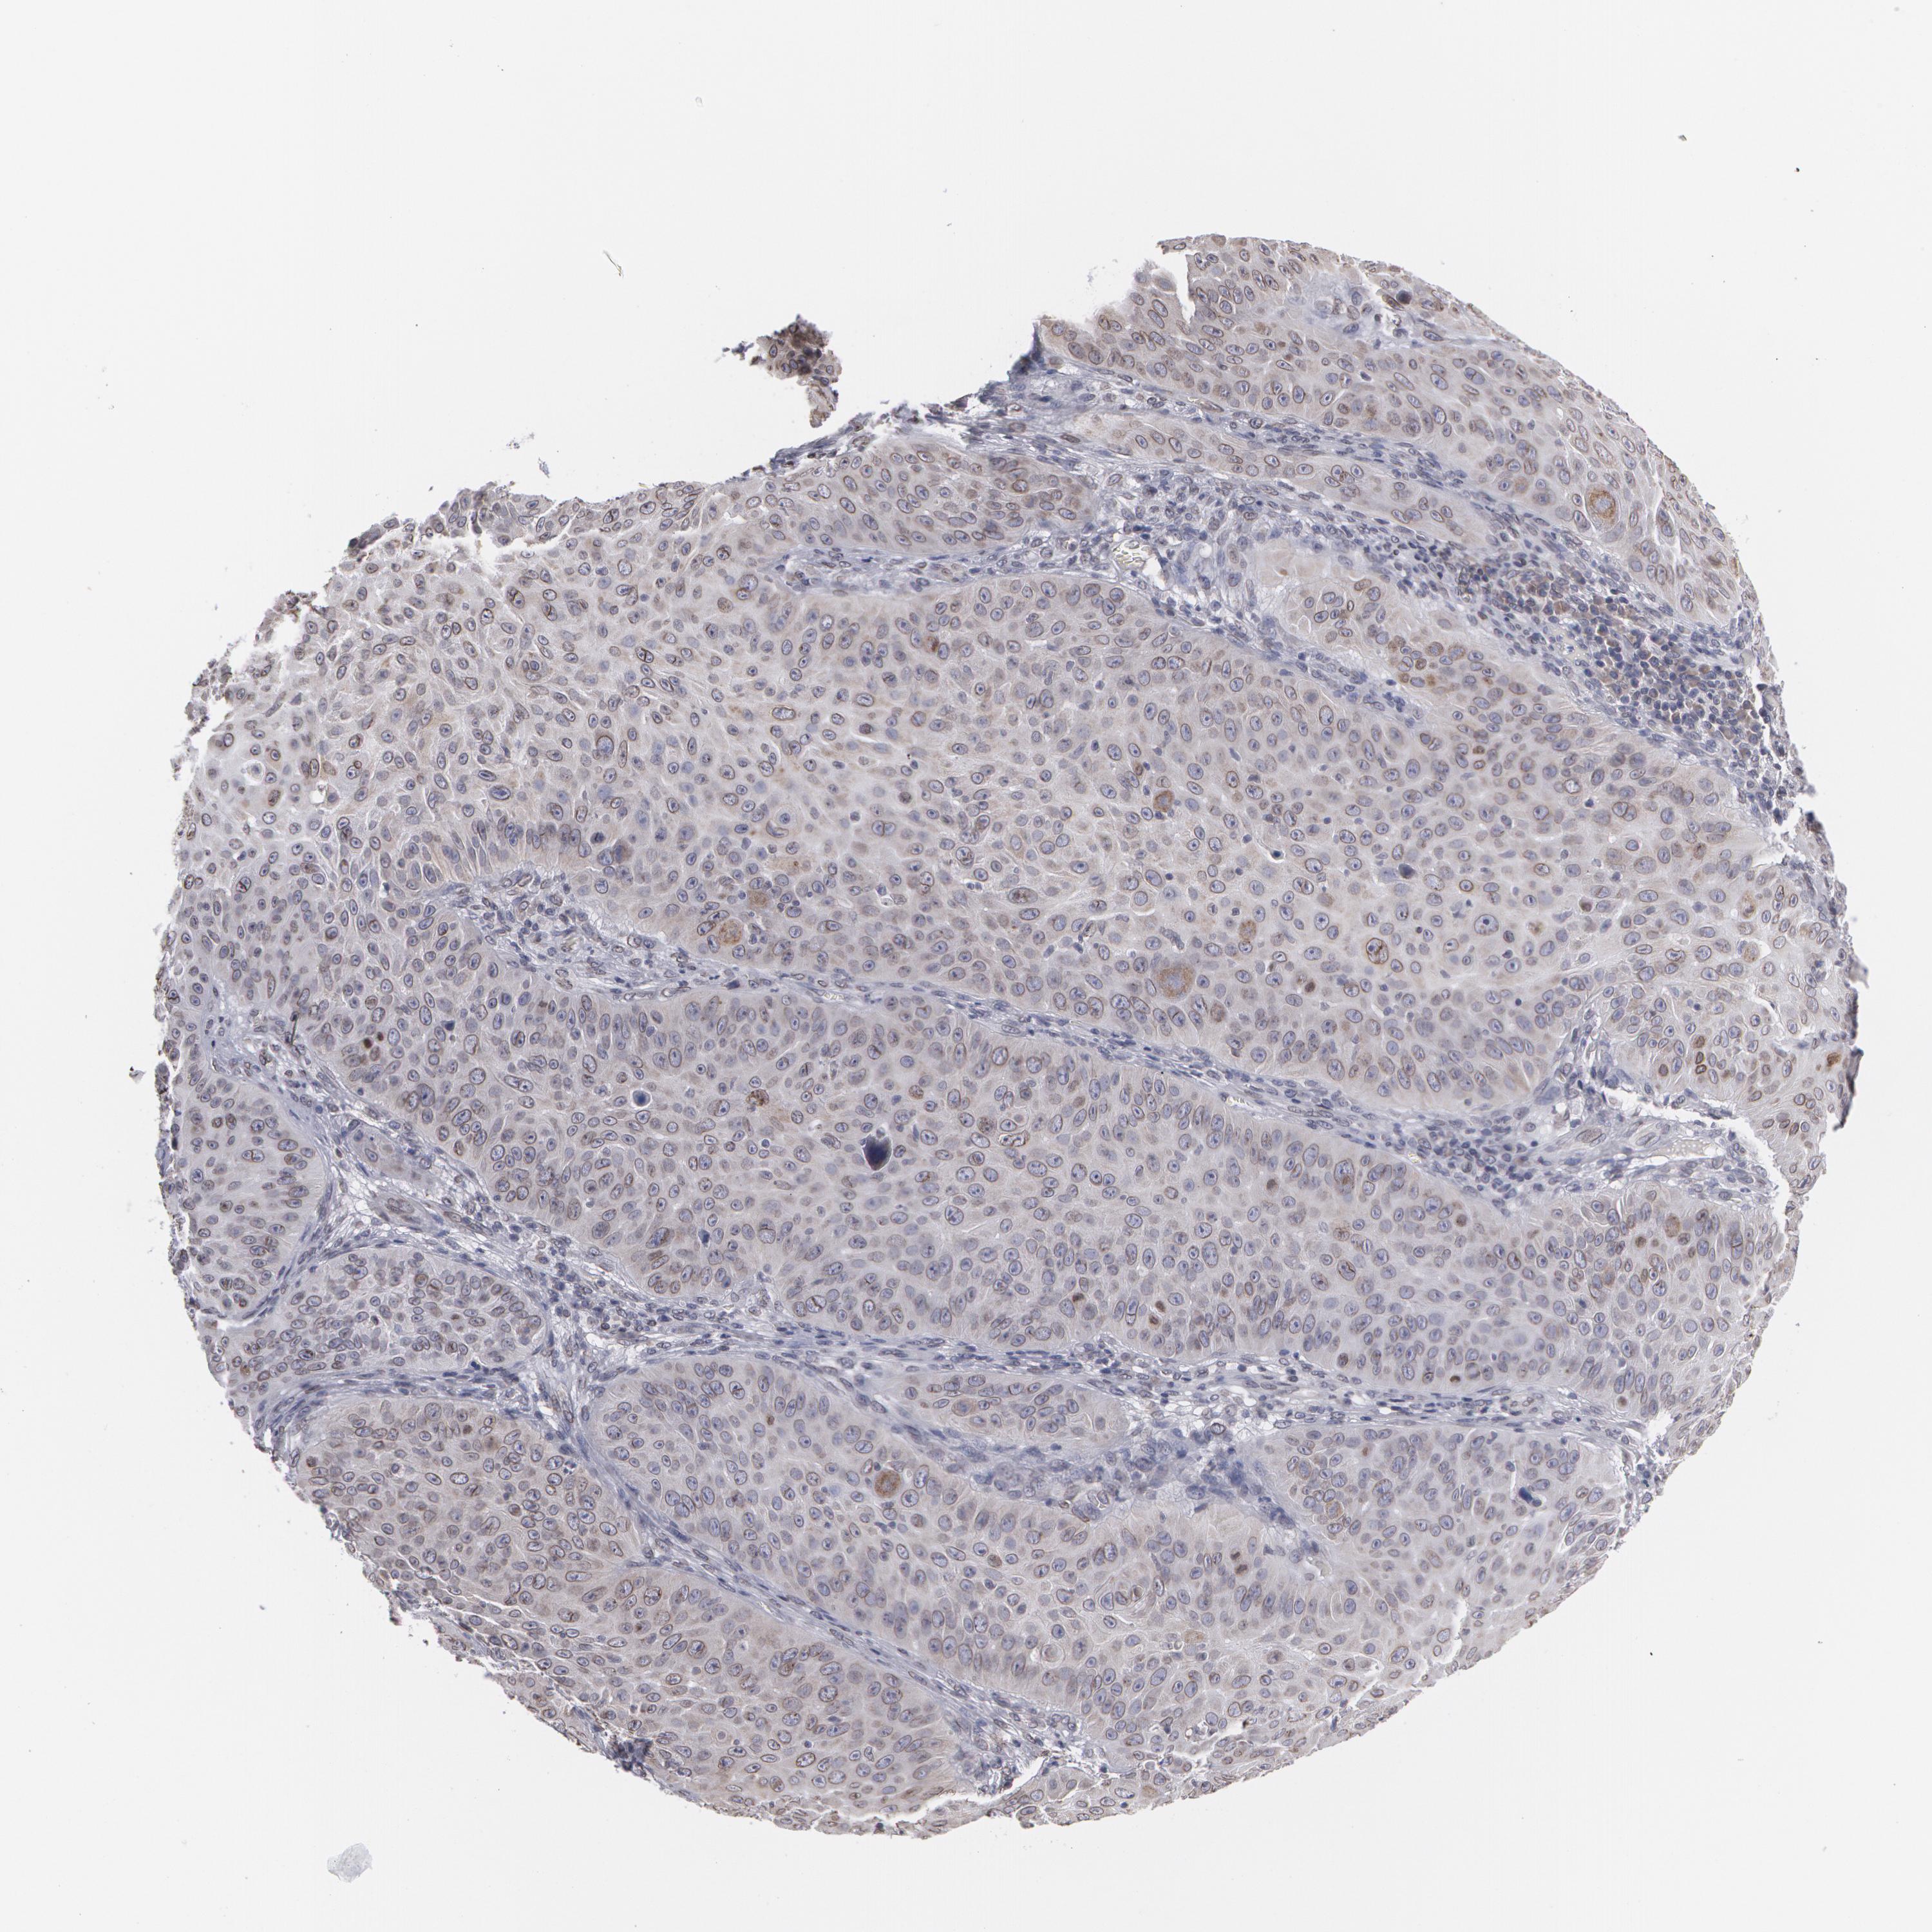

SKIN CANCER - Protein expressioni

A mouse-over function shows sample information and annotation data. Click on an image to view it in a full screen mode. Samples can be filtered based on level of antibody staining by selecting one or several of the following categories: high, medium, low and not detected. The assay and annotation is described here.

Antibody staining in the annotated cell types in the current human tissue is reported as not detected, low, medium, or high, based on conventional immunohistochemistry profiling in selected tissues. This score is based on the combination of the staining intensity and fraction of stained cells.

Each image is clickable and will lead to virtual microscopy that enables deeper exploration of all samples and also displays staining intensity scores, fraction scores and subcellular localization as well as patient and tissue information for each sample.

Antibody CAB001545

Basal cell carcinoma

Squamous cell carcinoma, NOS